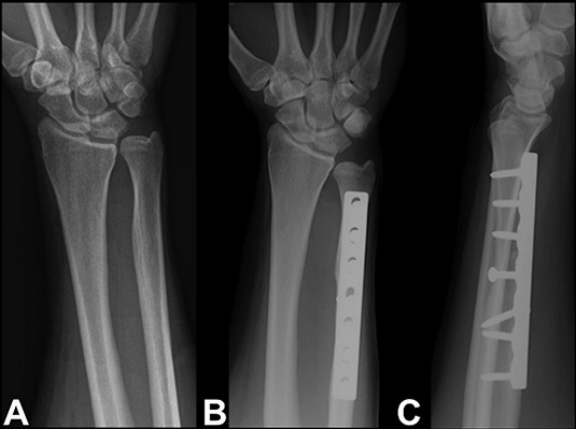

磁共振成像(MRI)检查也可发现相关异常,如月骨软骨软化、月三角韧带撕裂及磨损性三角纤维软骨复合体撕裂(图2)。

图2 磁共振成像扫描显示,在T1加权像和T2加权像中,月骨尺侧(箭头所示)出现信号改变,而在T2加权像中,三角纤维软骨复合体也出现信号改变。